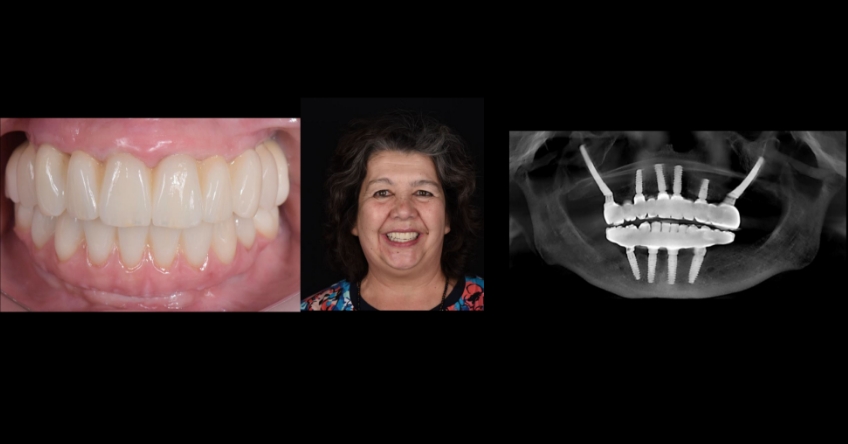

Our patient is a 66-year-old woman who presented with three remaining teeth in the maxillary arch and a fixed-hybrid temporary reconstruction in the mandible. She came looking for a second opinion regarding treating her maxillary arch.

Her previous dentist suggested a similar approach to what was done in the mandible, which entailed removing the few remaining teeth and removing bone and soft tissue to place four implants for a fixed-hybrid provisional restoration.

Even though she went through this protocol with her lower jaw, she wanted to know if there were alternatives to treat her condition in the maxilla because the bone and tissue removal aspect did not appeal to her. She was told elsewhere that this was the only predictable way of treating her condition.

Once the patient understood the nuances between graft vs. a graft-less solution, she opted for a combination of anterior and ZIs instead of grafting the sinuses.

Ultimately, the patient was treated using a combination of traditional and zygomatic implants, allowing her to transition into the definitive prosthesis uneventfully and in a reasonable time frame. This prosthetic design aimed to improve the distribution of occlusal forces and provide enhanced structural support for the final prosthesis.

ZIs, with or without traditional dental implants, are a safe and predictable first line of treatment compared to more time-consuming and financially burdensome traditional bone grafting approaches.

Comparing zygomatic implants (ZI) vs. bone grating can affect the outcome for your patient. The selection of the proper combination of traditional and ZIs is based on the amount of residual maxillary alveolar bone, the biomechanical requirements of the final dental implant rehabilitation, finances, and surgeon and restorative dentist preferences and experience. The most critical factor for success is the establishment of a prosthetically driven treatment plan between the surgeon and the restorative dentist.